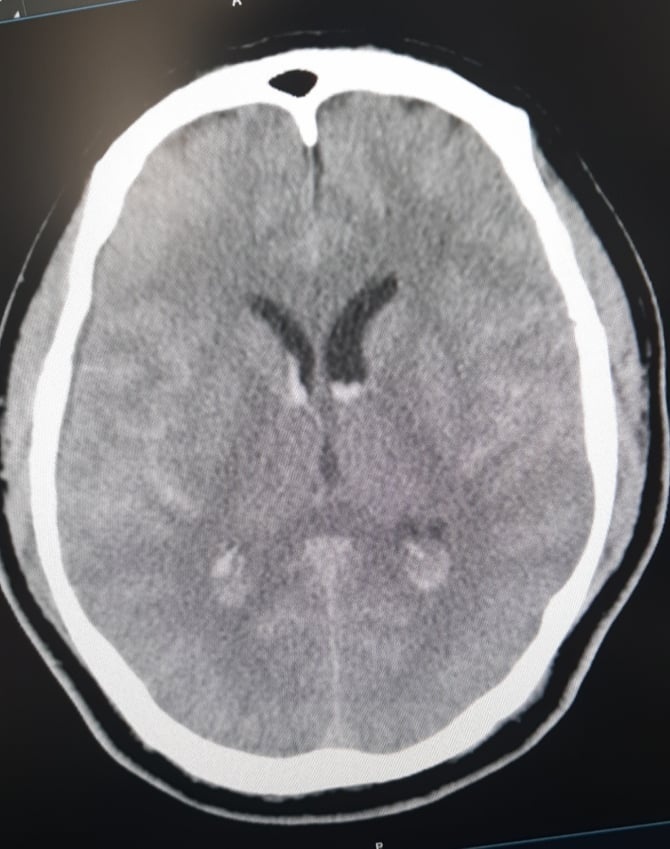

Bệnh nhân được chẩn đoán chảy máu não với các biểu hiện đau đầu, buồn nôn.

Trước đó, khi đang chơi golf ở Hòa Bình, bệnh nhân bỗng có cảm giác đau đầu dữ dội, buồn nôn, nôn nhiều. Ông nhanh chóng được đưa vào cấp cứu tại Bệnh viện Đa khoa tỉnh Hòa Bình. Tại đây, ông N. được chụp CT sọ não. Các bác sĩ chẩn đoán bệnh nhân bị chảy máu dưới nhện.

Hình ảnh chụp não bệnh nhân Hàn Quốc. Ảnh: BVCC.